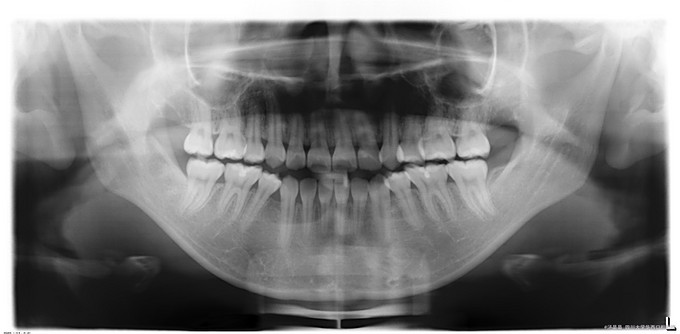

正颌术后复诊,患者因下颌前突一年前在我院正颌外科行BSSRO+双侧下颌骨去骨皮质术+坚固内固定术+牙弓夹板栓扎术,今复诊要求拆钛板

口内检查:上下牙弓关系协调,前牙正常覆合覆盖,后牙正中咬牙合,腔卫生状况良好,全口牙未见明显异常。下颌体双侧扪及钛板,颈部浅表淋巴结未触及。

诊断:正颌术后钛板钛钉存留,在手术室全麻下行“双侧下颌骨钛板钛钉取出术+右下颌骨部磨削术+双侧下颌邻近瓣转移修复术”。手术经过顺利,麻醉满意